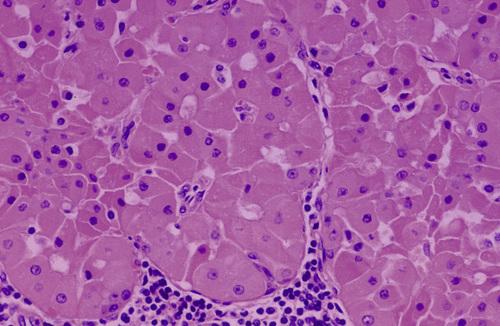

Parotid tumor demonstrating sheet of granular, basophilic serous acinar cells. The most characteristic cell is one with features of the serous acinar cell, with abundant granular basophilic cytoplasm and a round, darkly stained eccentric nucleus.

acinic cell carcinoma

High-power view of serous cells with basophilic, granular cytoplasm. The most characteristic cell is one with features of the serous acinar cell, with abundant granular basophilic cytoplasm and a round, darkly stained eccentric nucleus.

acinic cell carcinoma